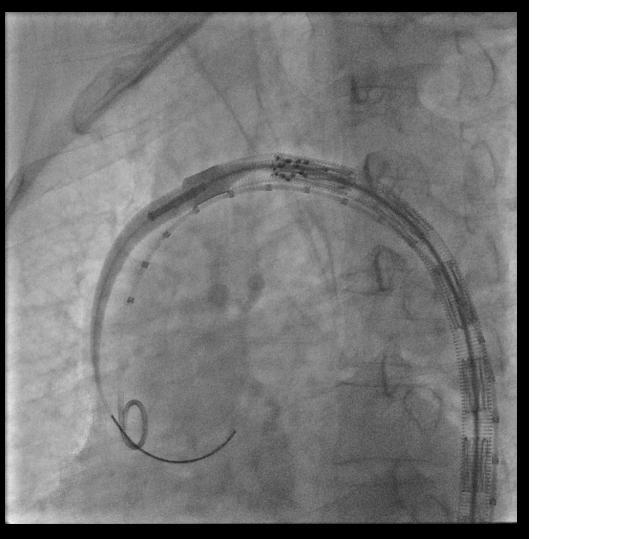

EVAR